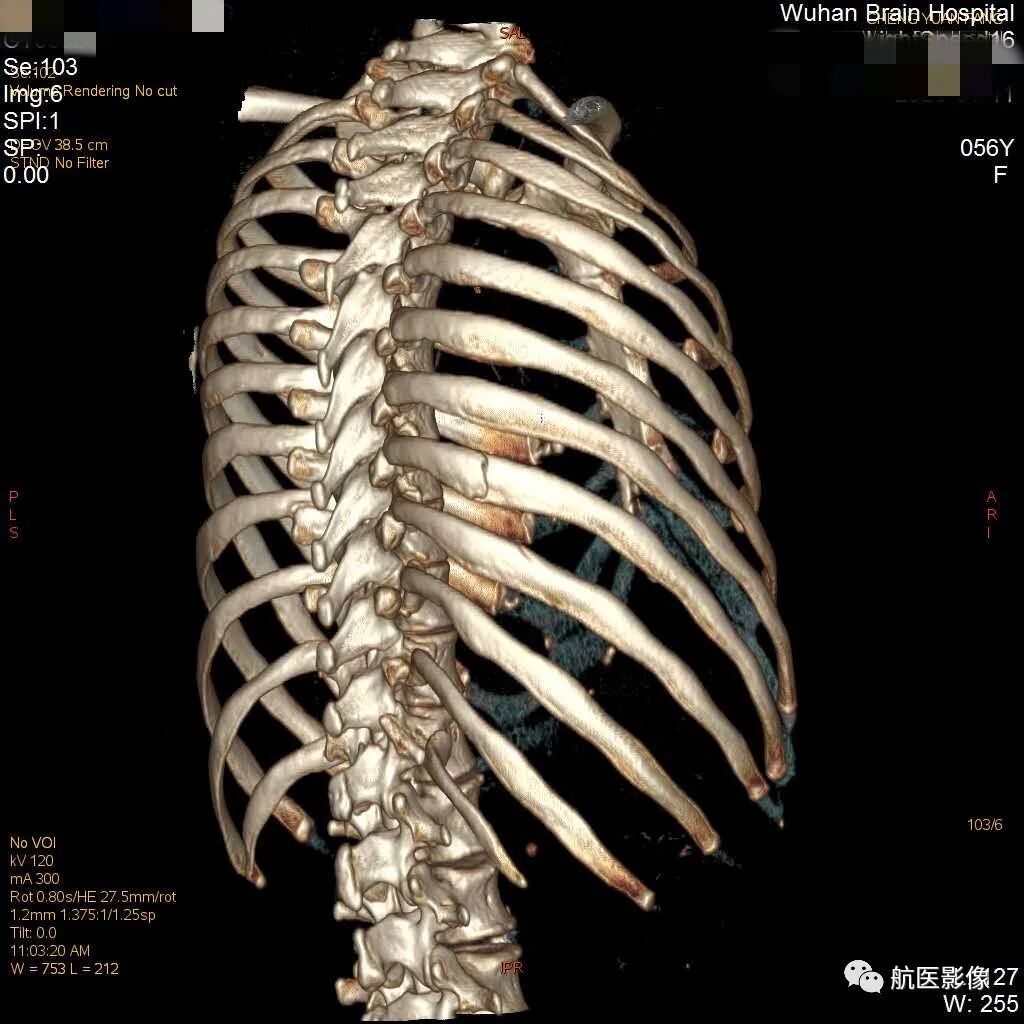

双侧肋骨共有12对,解剖形态不规则呈半弧形,由于肋骨解剖特点的复杂性,其走行的特殊性且环绕呈圆桶形,肋弓弯曲大,和前后多脏器互相重叠,故肋骨X摄片不易清楚显示细微、无明显移位的肋骨骨折,而横断面CT限于连续性、定位性不佳,不易确定具体肋骨骨折根数,而三维成像可将全部肋骨完整立体再现,并且可进行旋转观察,定位效果好,对肋骨骨折的显示具有重要意义,肋骨骨折的根数、骨折的类型对法医学鉴定结果影响尤其重要。

多层螺旋CT具有快速连续的扫描方式和容积性数据采集的特点,并具有多角度、多平面重组的后处理功能,能任意角度地旋转观察损伤部位情况,识别细微的肋骨骨折;CT扫描横轴位可显示骨折,但不能显示骨折全程。

VR是通过容积数据时所有像素总合的图像显示,利用了所有扫描信息,是一种较高形式的重建方式,并能通过任意手工选择层面,任意方位进行切割和旋转,较为满意地显示出骨折线、移位,是一种对骨折后处理较常用的CT后处理技术。VR三维重建图像提供近似解剖结构的图像,定位准确,空间立体感强。MPR可行冠状、矢状和轴位重建图像,对胸部损伤行多剖面观察,可清楚显示断端周围软组织肿胀;能随时在VR、MPR、骨窗及肺窗间进行转换。